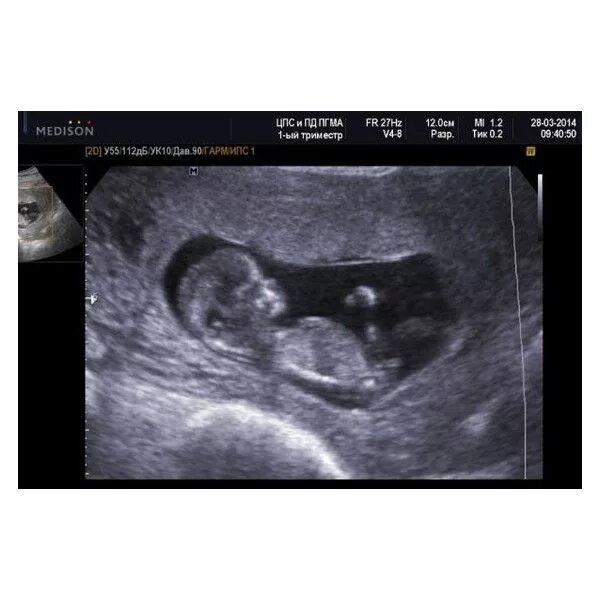

12 недель и два дня